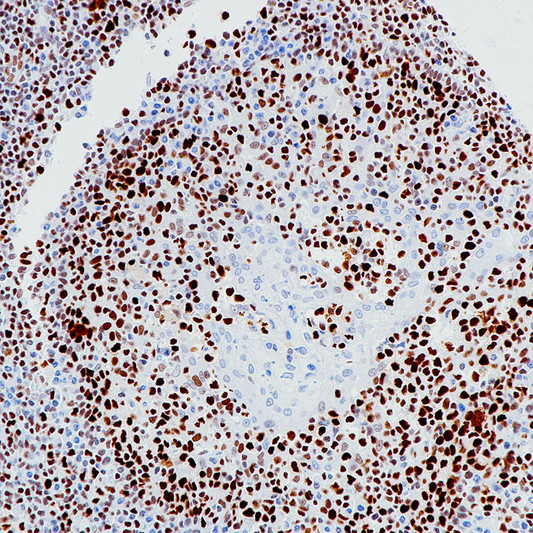

Anti-MCM2 antibody [BP6220] (STJA0037717)

| Short Description | Rabbit monoclonal anti-MCM2 for use in IHC-P in Human samples. Datasheet included with dilution recommendations, and related reagents. |

| Applications | IHC-P |

| Dilution Range | IHC 1:100-1:200 |